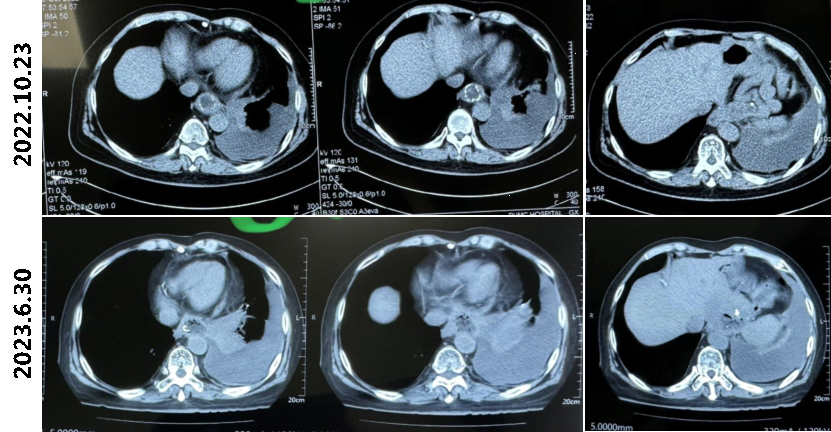

患者进食红心火龙果约1小时后,胸水呈粉色;患者于本院胸水培养见白念珠菌,而白念珠菌难以由肺内播散至胸膜;外院胸水及BALF培养见白色假丝酵母菌,BALF-NGS提示白色念珠菌,且患者既往有食管手术史,不能排除食管-胸膜瘘可能,我们追踪了患者2022年的胸部CT。可以看出,患者2022年胸部CT纵隔窗见明显食管-空肠吻合口缝合痕迹,而自2022.6.30起,吻合口处缝合脱落。